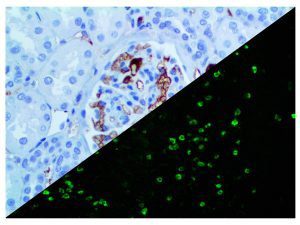

It is the ICU physician who is most likely to witness one of the deadliest manifestations of the abnormal immunological response, the cytokine storm syndrome (CSS). This response is also referred to by some as the cytokine release syndrome (CRS). CSS is characterized by continuous activation and expansion of macrophage and lymphocyte populations, which secrete large amounts of cytokines, causing the cytokine storm. This massive cytokine release is akin to hemophagocytic lymphohistiocytosis (HLH) disease, a syndrome characterized by initial unchecked and persistent activation of cytotoxic T lymphocytes and NK cells.

Clinical and laboratory manifestations of HLH include fever, enlarged liver and/or spleen, neurologic dysfunction, coagulopathy, liver dysfunction, cytopenias (i.e., low levels of erythrocytes, leukocytes, and/or platelets), hypertriglyceridemia, hyperferritinemia, hemophagocytosis, and eventually diminished NK cell activity as the immune system becomes progressively paralyzed. HLH can be familial (primary HLH) or secondary to another disease process (sHLH), such as rheumatic disease, in which it is referred to as macrophage activation syndrome (MAS, characterized by elevated ferritin).